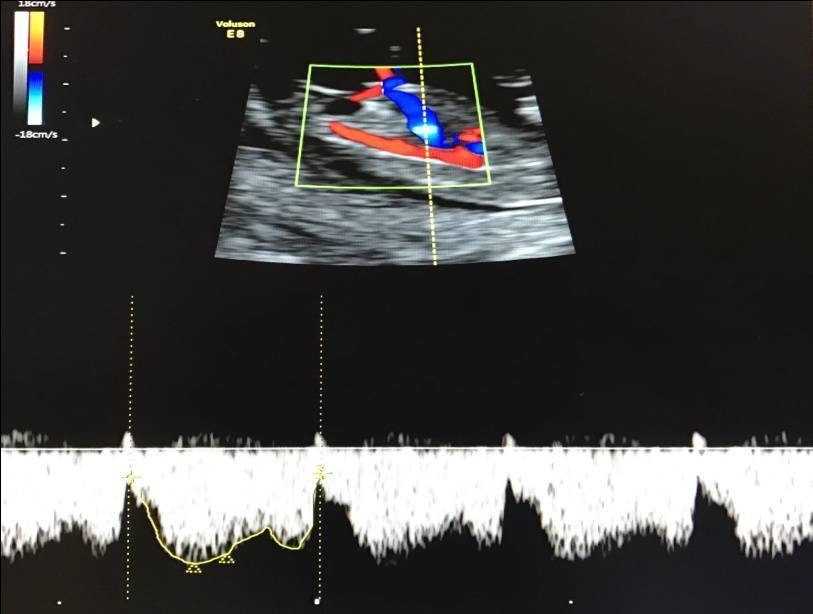

– кровоток в венозном протоке – это маленький сосуд в печени плода. При обратном (ретроградном) токе крови в данном сосуде можно предположить, что у плода хромосомный синдром, либо врожденный порок сердца.

Нормальный кровоток в венозном протоке

Но важно правильно получить этот кровоток и дать ему оценку. Для этого требуются определенные навыки и квалификация врача, которые подтверждаются ежегодной сертификацией FMF.